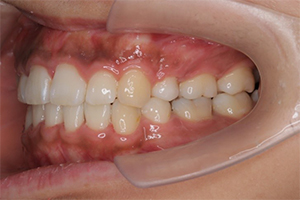

矯正治療のCASE 04

Before

After

-

- 主訴

- 歯並びがガタガタしていて清掃しにくい

- 治療内容

- ラビアル矯正(表側)

抜歯あり

- 治療費用

- 88万円~(税込)

- 治療期間

- 20か月

【リスク・副作用】

歯の痛み、口内炎、歯磨きがしにくいことによるむし歯や歯周病のリスク、歯根吸収や歯の変色、後戻りなどの副作用があります。